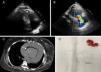

Advances in magnetic resonance imaging (MRI) over the past two decades have led to it becoming an increasingly attractive imaging modality. With the growing number of patients treated with permanent implanted or temporary cardiovascular devices, it is becoming ever more important to clarify safety issues with regard to MRI examinations in patients with these devices. A 57-year-old woman was admitted to the emergency department with a one-month history of progressive anasarca. Her medical history included subarachnoid hemorrhage and a deep vein thrombosis in the same hospitalization period, treated with inferior vena cava (IVC) filter placement (ELLA®, Hradec Králové, Czech Republic). The initial echocardiographic assessment showed hyperechoic linear images in the right chambers (Figure 1A) and severe tricuspid regurgitation (Figure 1B). Chest computed tomography confirmed the hypothesis of IVC filter migration, demonstrating intracardiac metallic fragments (Figure 1C). After clinical stabilization with intravenous diuretics, the patient underwent cardiac surgery and thrombus and IVC filter fragments were removed (Figure 1D), in addition to tricuspid valve repair, followed by successful recovery. After a thorough review of the patient's clinical history, it was discovered that she had recently undergone a brain MRI in another institution (about two months before symptom onset), without mentioning implantation of the IVC filter about nine months before. Although this MRI had been performed late, it was probably the cause of IVC filter migration, highlighting the safety concerns with this examination in patients with this device.